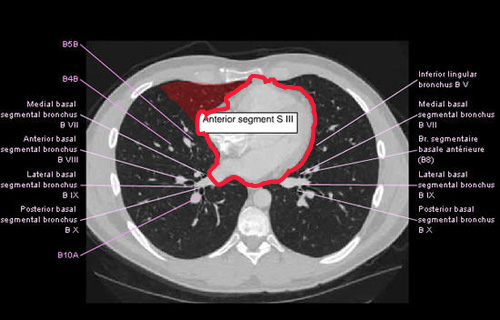

Images with red objects have the red object as the heart. Of note, the sternum does not completely cover the heart, the intercostal spaces are greater than the ribs, and on the silhouette, the heart is 9.52% of the boxed area.